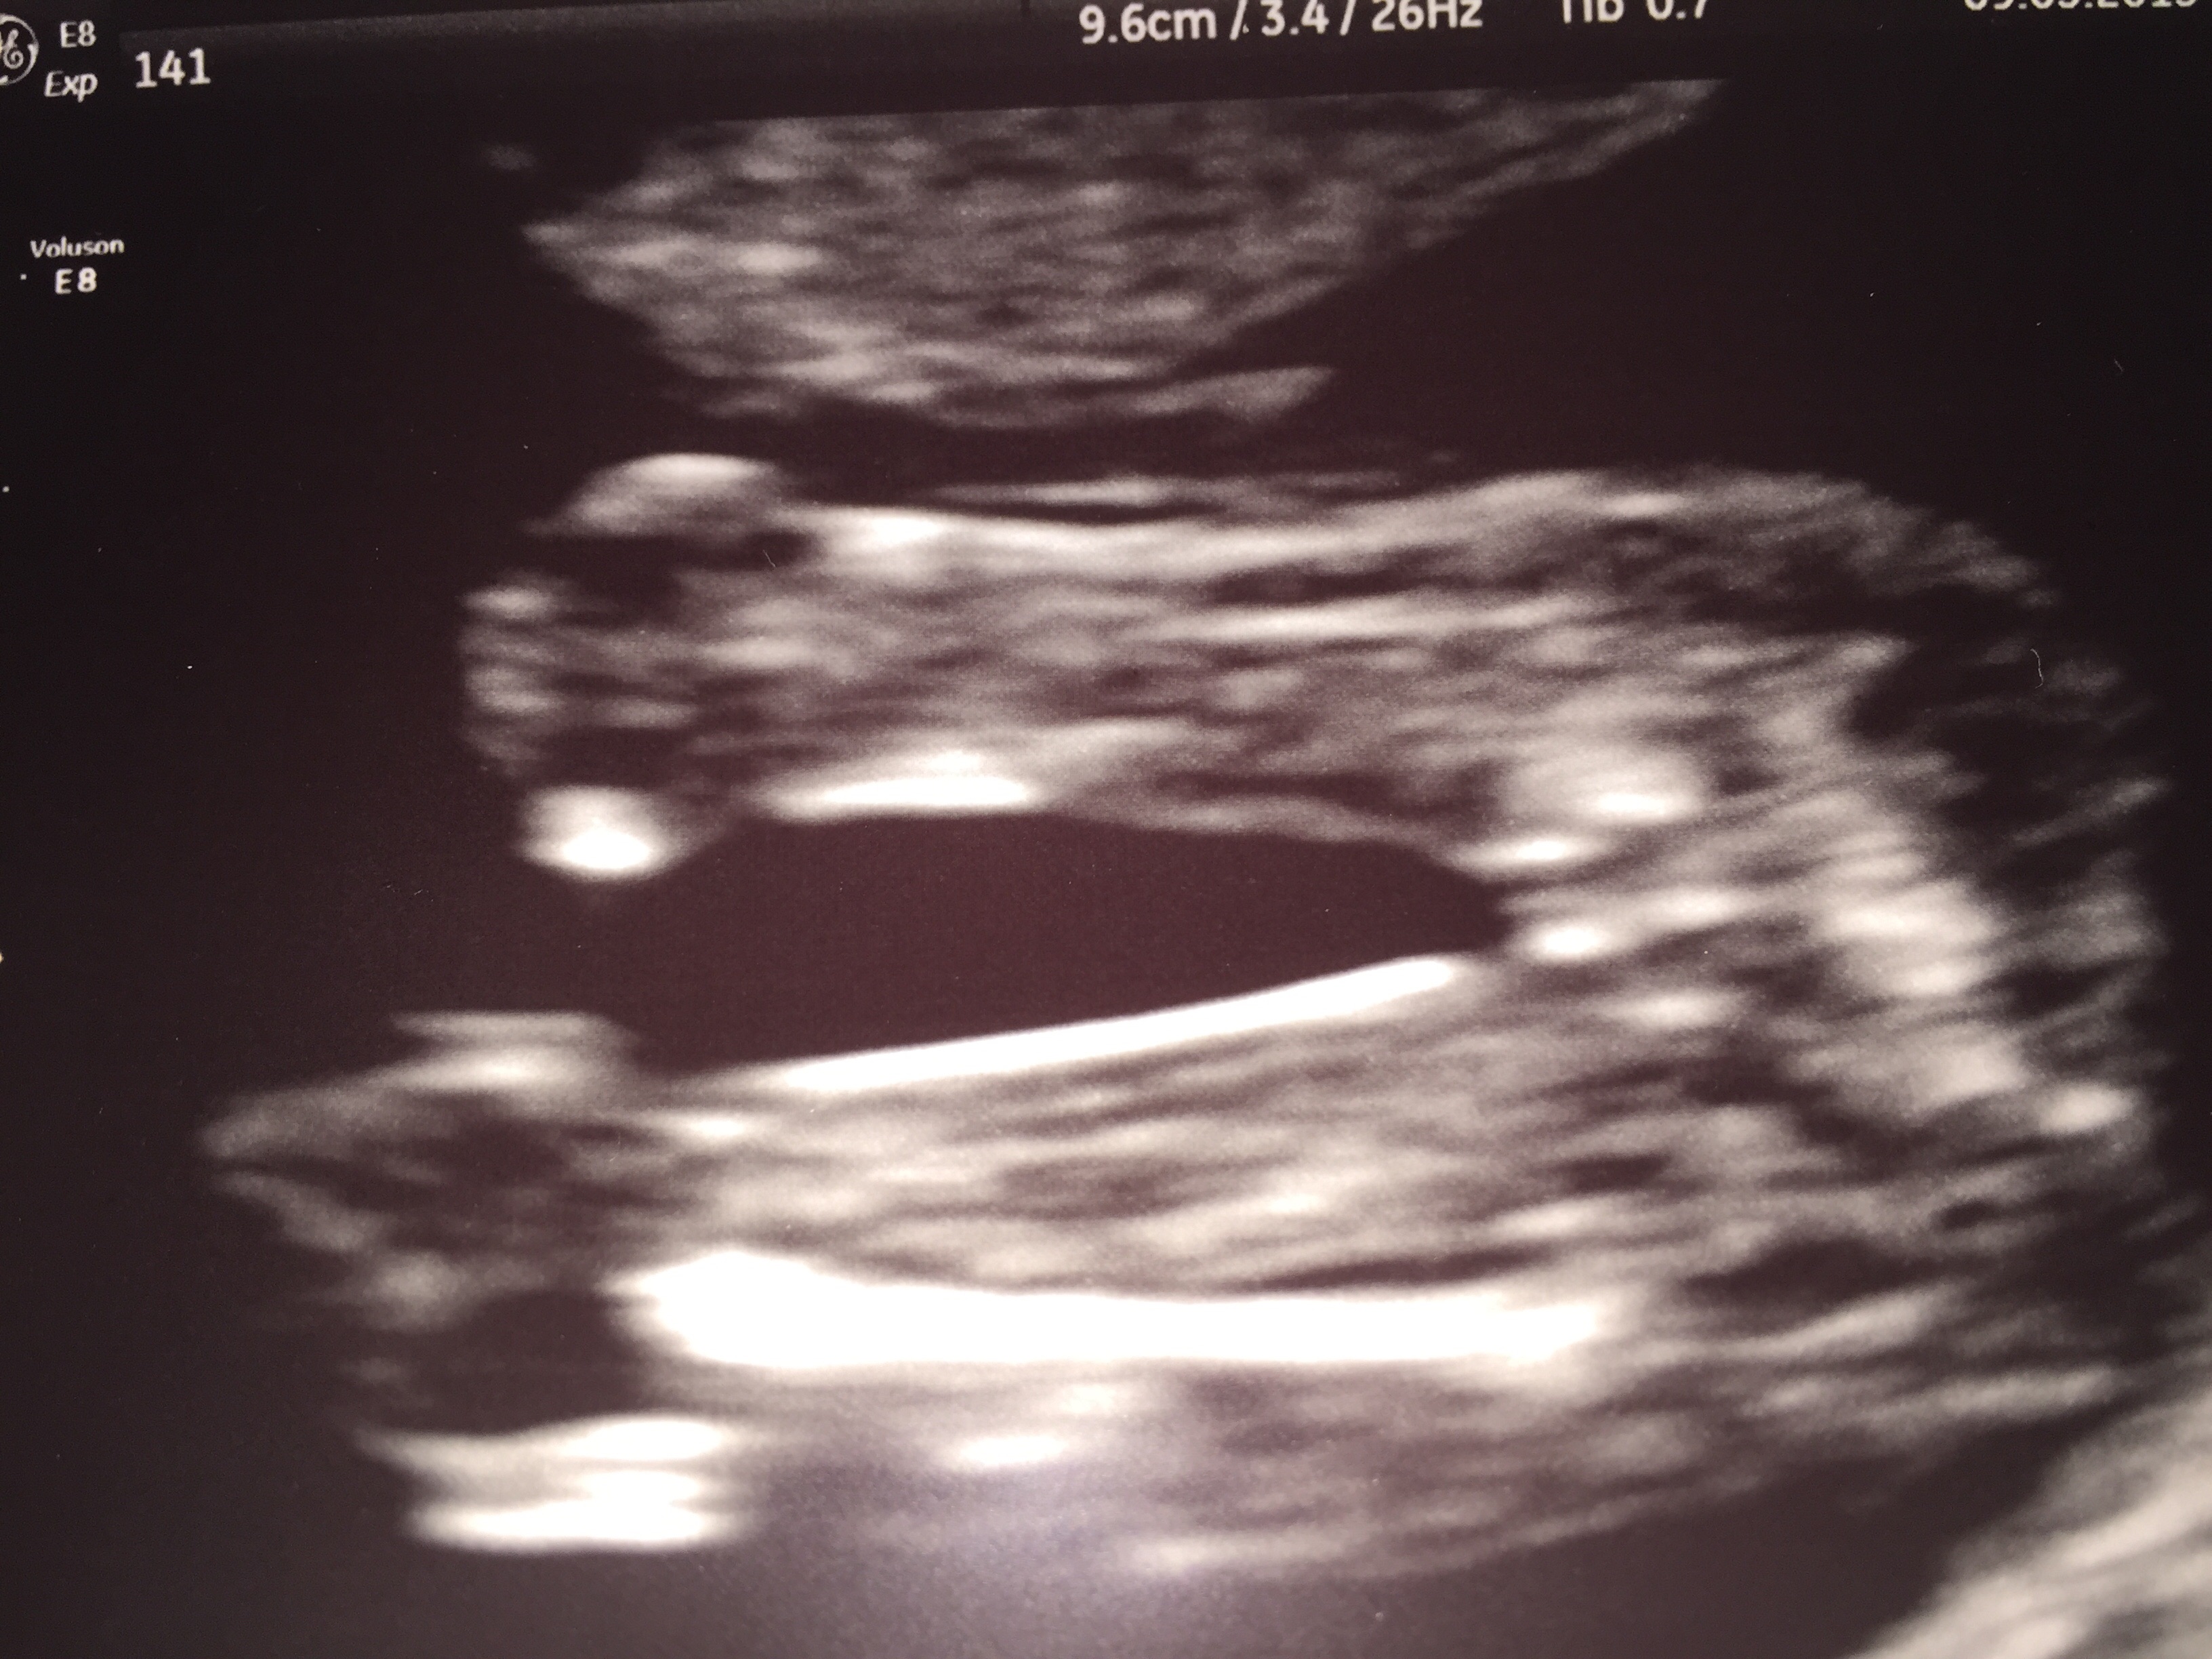

Hi this is my scan 12+6 feel free to guess Attachment 25114Attachment 25115

I think might be a boy

Not clear enough sorry!

It's because you're nearly 13 weeks and the nub isn't THAT risen, only very slightly angled. But I wouldn't be surprised if it is a boy either.

It's a little girl :) x